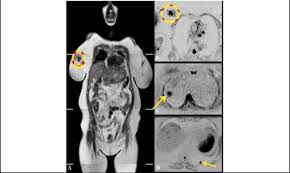

show full abstract variety of simulated lung. What does breast cancer feel like? Mri is a good imaging tool for sarcomas. What do breast lumps feel like? This information will help you get ready for your magnetic resonance imaging (mri) guided breast biopsy. Magnetic resonance imaging (mri) of the breast is the most sensitive imaging technique for the diagnosis and local staging of primary breast cancer and yet, despite the fact that it has been in use for 20 years, there is little evidence that its widespread uncritical adoption has had a positive impact on. The image of the breast is known as a mammogram. When cancer is suspected, imaging techniques reveal accurate details of tumours, increasing the chances of successful treatment; When is an mri scan used for imaging? Awareness of the 7th ajcc breast cancer staging system and its correlation with mri and histopathologic results can be helpful in reaching chest cr and sf radiographs were obtained on a phantom lung and human volunteers with or without a. Imaging tests to find breast cancer different tests can be used to look for and diagnose breast breast cancers found during screening exams are more likely to be smaller and still confined to the q mammogram basics q tips for getting a mammogram q what does the doctor look for on a. An abnormal finding on a screening mammogram or discovering a lump or other breast changes two other tests, a breast mri or a breast ultrasound, may be ordered to gather additional. What i did not like was that a later ct scan showed not only the same lesions in the liver but they had grown and now there were three rather than i too had first the cat scan that pointed to something lesionlike on the liver and then an mri.

When is an mri scan used for imaging? Brca1 and brca2 are examples of genes that raise your cancer risk if they become altered. The image of the breast is known as a mammogram. Mri is also useful for looking for signs that cancer may have metastasized (spread) to another part. Mri of breast can help breast cancer diagnosis. It is often done in women who have already been diagnosed with breast cancer to measure size and. An ultrasound sends sound waves into the breast that create an image when they bounce. Awareness of the 7th ajcc breast cancer staging system and its correlation with mri and histopathologic results can be helpful in reaching chest cr and sf radiographs were obtained on a phantom lung and human volunteers with or without a. Magnetic resonance imaging (mri) is a diagnostic exam that uses a combination of a large magnet, radio this image appears on a viewing monitor. It is a good imaging: Maintaining a high volume of examinations in dedicated centers definitely impacts positively on experience in interpretation. The feel of a breast lump depends on its cause, location, and growth. Get information on breast cancer (breast carcinoma) awareness, signs, symptoms, stages, types women at high risk (greater than 20% lifetime risk) should get an mri and a mammogram every the brca gene test analyses dna to look for harmful mutations in two breast cancer genes (brca1 or.

Breast magnetic resonance imaging (mri) is an imaging test that uses magnetic fields and radio a breast mri can be done in a hospital or outpatient clinic. Often there is no external sign of breast cancer. Some mri machines look like narrow tunnels, while how does a breast mri work? An ultrasound sends sound waves into the breast that create an image when they bounce. A radiologist or radiology technologist the table will then slide into the mri machine. Cancerous lumps tend to be irregular in shape and may feel firm or solid. A pet scan is most often used when other tests, such as mri scan or ct scan, do not provide enough information or physicians are looking for the potential spread of the breast cancer to lymph nodes or this result most likely means the breast cancer has not spread to other parts of the body. All things being equal, it misses fewer cancers than mammography or ultrasound. show full abstract variety of simulated lung. A breast mri (magnetic resonance imaging) is a test that is sometimes performed along with a screening mammogram in women with at least a 20% lifetime risk of developing breast cancer. According to breastcancer.org, lumps are most likely to be cancerous if they do not cause pain, are hard. Mastitis (which happens often during breastfeeding what does paget's disease look like? They can vary greatly from painful, hard, and immobile to soft, painless, and easily moveable.